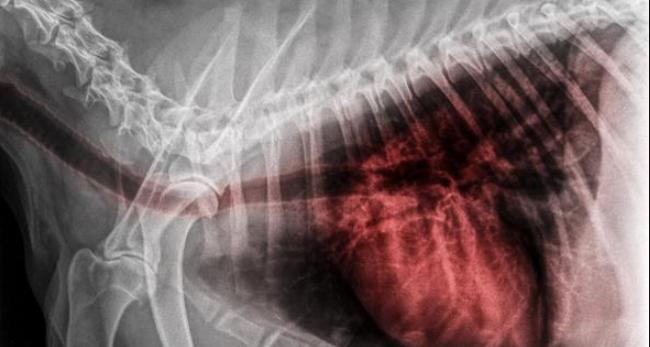

O edema pulmonar cardiogênico em cães é aquele que tem origem devido a uma doença cardíaca. Quando o coração falha, é produzido um refluxo de sangue para os pulmões, fígado, extremidades, etc. Esse refluxo aumenta a tensão nas veias, o que faz com que o líquido seja filtrado para os pulmões ou para a cavidade abdominal. Com líquido nos pulmões, o cachorro tosse. Assim, o edema pulmonar indica uma insuficiência na parte esquerda do coração. Por outro lado, quando a lesão está na parte direita, o líquido se acumula no abdômen, causando ascite e edemas nas patas e também na cavidade torácica, o que é conhecido como derrame pleural. Se o líquido se acumula nos bronquíolos do pulmão, o cachorro pode apresentar a expectoração de um líquido avermelhado e espumoso. Nos cachorros com esse problema, é comum notar cardiomegalia e edema pulmonar. A cardiomegalia é o aumento do tamanho do coração.

Para o diagnóstico são utilizados exames diagnósticos como a auscultação, radiografia ou ultrassonografia de tórax, além de exames de sangue. O eletrocardiograma, o exame da urina e a medição da pressão arterial também são exames importantes para saber se um cachorro tem edema pulmonar. Nos animais em casos mais graves, é preciso ter um cuidado especial, já que qualquer manipulação pode agravar a crise respiratória.